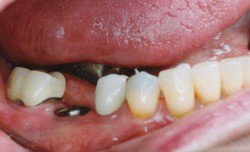

• اول به اين معني است که دندانپزشک قطعه اول ايمپلنت يعني فيکسچر را در داخل استخوان فک بيمار قرار داده و هنوز جاي دندان طبيعي خالي مي باشد. در اين حالت بيمار بايد دو الي سه ماه صبر کند تا فيکسچر با استخوان فک پيوند برقرار کند و سپس مراحل بعدي انجام شود.

• دوم يعني دندانپزشک فيکسچر را در استخوان فک قرار داده است و بعد از گذشت دو الي سه ماه، قطعه دوم ايمپلنت را که هيلينگ نام دارد روي فيکسچر بسته تا در اطراف آن لثه شکل بگيرد. سپس قطعه سوم (اباتمنت) به همراه دندان چيني (ساخته شده توسط دندان ساز) که تکميل کننده ايمپلنت مي باشد، به جاي هيلينگ قرار مي گيرد. دندانپزشک دندان چيني را روي اباتمنت مي چسباند. در اين زمان بيمار مي تواند همانند دندان طبيعي از دندان مصنوعي خود استفاده کند.